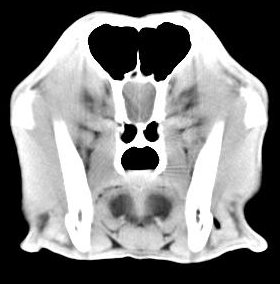

imágenes de TC en el perro | ||||||||||

ejemplo de imágenes de TC en el perro. Nótese la celulitis en la región parotídea izquierda | ||||||||||